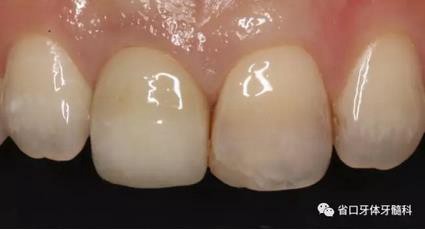

(4)最終修復(fù)與隨訪:經(jīng)過(guò)3個(gè)月左右的塑形,上頜右側(cè)中切牙臨時(shí)修復(fù)固位良好,菌斑控制良好,近遠(yuǎn)中齦乳頭充盈良好,齦緣水平及形態(tài)與 鄰牙相對(duì)稱。牙齦塑形穩(wěn)定后,以臨時(shí)修復(fù)體制作個(gè)性化轉(zhuǎn)移桿并取模轉(zhuǎn)移,并以原廠氧化鋯基臺(tái)制備個(gè)性化基臺(tái)及全瓷冠。正確就位最終基臺(tái),加 力30N·cm。制備粘接代型,去除多余粘接劑,以Unicem粘接固位上頜右側(cè)中切牙全瓷修復(fù)體。固化穩(wěn)定后,再次確定咬合無(wú)干擾。最終修復(fù)完成后 隨訪3個(gè)月及6個(gè)月,上頜右側(cè)中切牙種植修復(fù)固位穩(wěn)定,近遠(yuǎn)中齦乳頭充 盈良好,唇側(cè)齦緣水平穩(wěn)定。

圖33 就位全瓷冠

上頜右側(cè)中切牙修復(fù)體固位良好,牙齦乳頭充盈良好,齦緣水平對(duì)稱 修復(fù)體與對(duì)側(cè)同名牙協(xié)調(diào)一致。外觀笑容美觀協(xié)調(diào)?;颊邼M意。X線檢查示 上頜右側(cè)中切牙種植體周穩(wěn)定骨質(zhì)包繞,唇側(cè)骨板>2mm,相鄰牙槽骨高度穩(wěn)定,基臺(tái)及修復(fù)體就位良好。分別根據(jù)Furhauser的PES和Bulser的WES 進(jìn)行美學(xué)評(píng)分,總分值為20,美學(xué)效果良好。